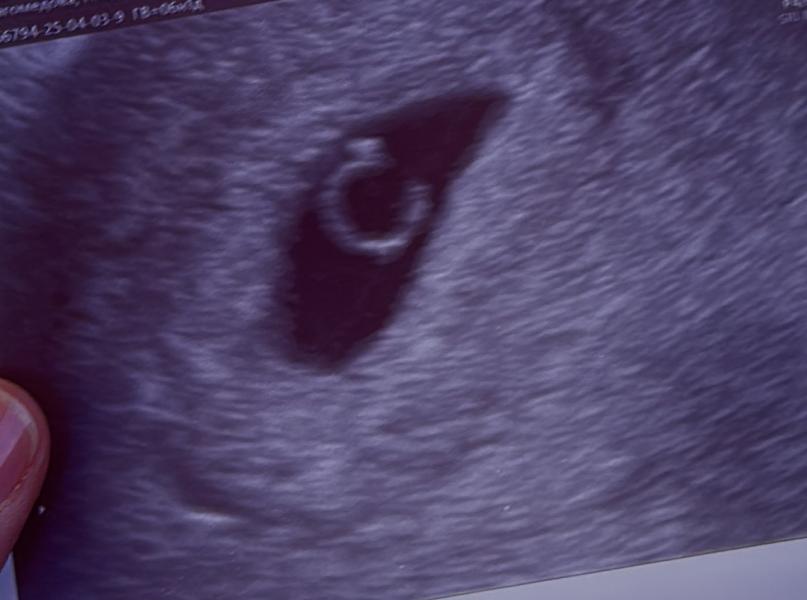

Самое дорогое колечко в моей жизни - Альхамдулиллах!

самое дорогое колечко в моей жизни 🤍 Альхамдулиллах ⛅️

Уже было слышно сердцебиение?😍

Даа, только началось ☺️ 118 уд/мин. Через неделю пойду снова чтобы уже отчетливо послушать 🤍